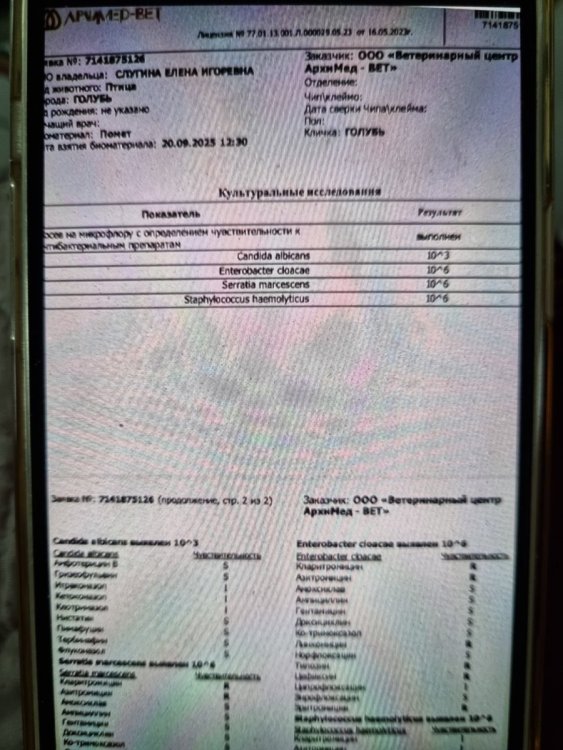

Это не у меня только так, вот люди в соседней теме сдавали параллельно в двух лабораториях, в одной лаборатории есть чувствительность к доксициклину, в другой нет